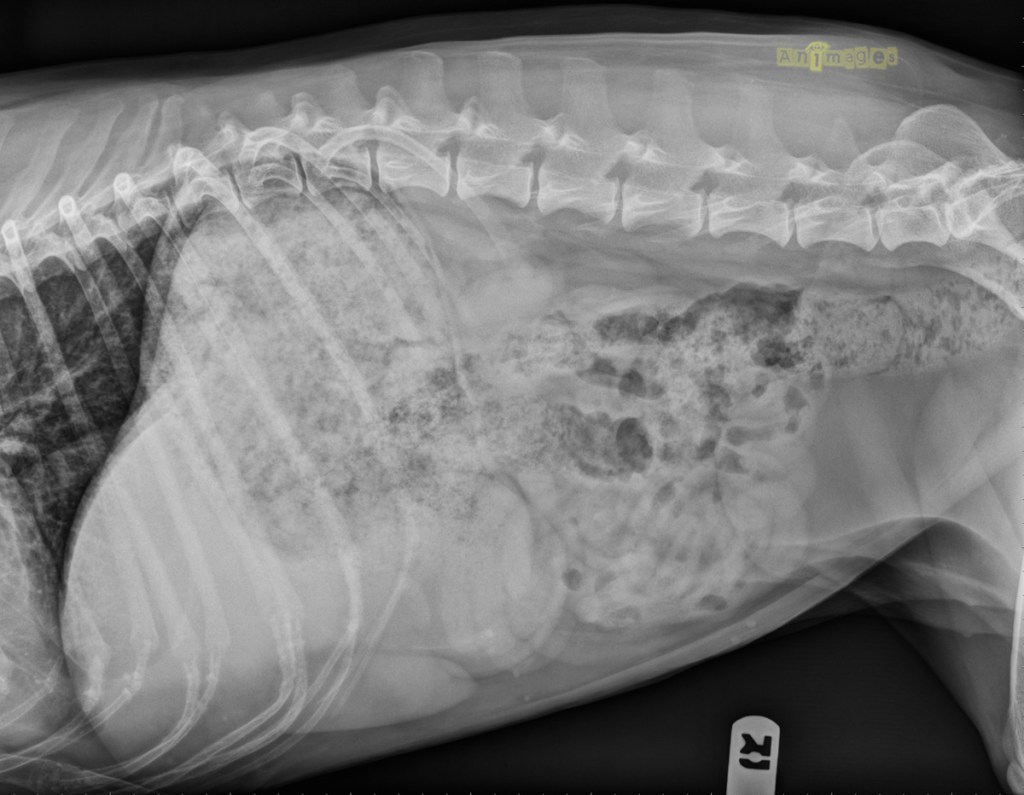

laterale_animages